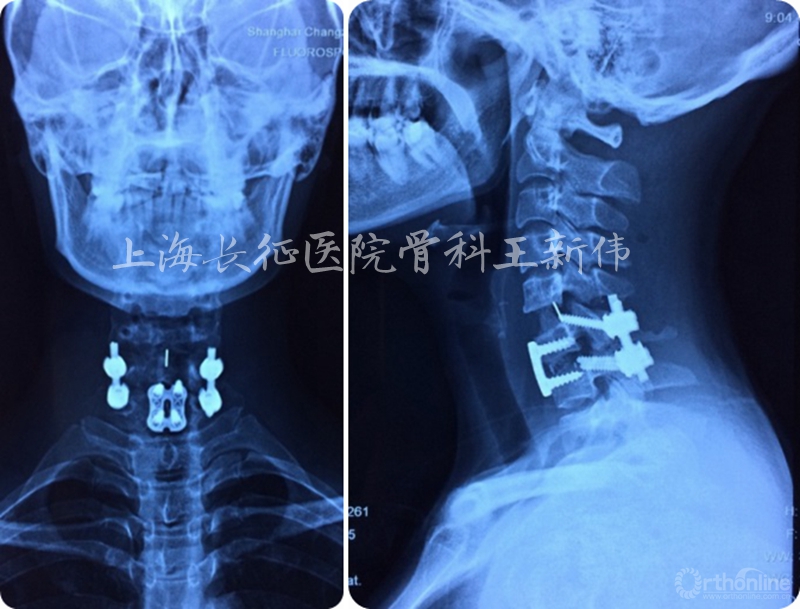

术后颈椎正侧位X线片

术后颈椎MRI平扫,见颈椎曲度及脊髓受压均已恢复